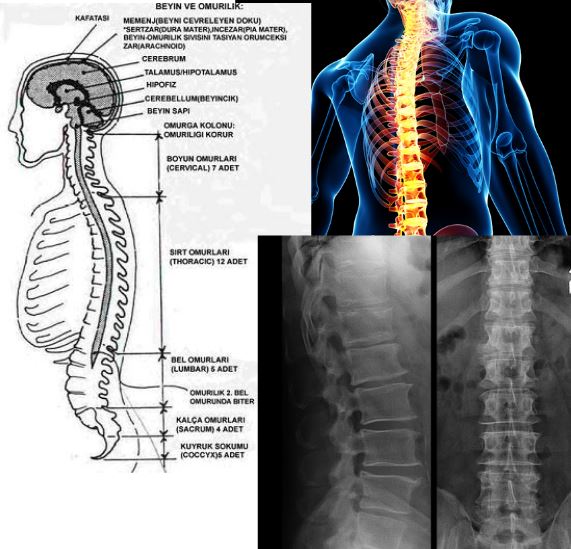

Omurga Anatomisi Resimli Anlatım, Columna vertebralis - Omurga Anatomisi, 35.11 MB, 25:34, 29,119, MC Anatomi, 2020-10-28T14:39:54.000000Z, 19, OMURGA EĞİTİMİ ANATOMİSİ | PilateSystem, www.pilatesystem.com.tr, 900 x 1125, jpeg, WebNormal omurga kafatasından başlayıp omurgada sonlanan toplam 33 omur ( 7 boyun, 12 sırt, 5 bel, 9 kuyruksokumu) parçasından oluşur. Bu omurlar arasında disk adı. WebOmurga, kafatası tabanından başlayıp, boyun ve tüm gövde boyunca uzanan lingitudinal bir kemik dokudur. Omurga, rijit bir kemik sütunu olmaktan ziyade yetişkinlerde 26 adet. WebOmurga Anatomisi Bu bölümlerde 7 boyun, 12 sırt, 5 bel omuru bulunur. Bel omurlarının hemen altında embriyolojik olarak omurga yapısındaki sacrum kemiği ve onun da altında., 20, omurga-anatomisi-resimli-anlatim, Ürün İncelemeleri WebNormal omurga kafatasından başlayıp omurgada sonlanan toplam 33 omur ( 7 boyun, 12 sırt, 5 bel, 9 kuyruksokumu) parçasından oluşur. Bu omurlar arasında disk adı. WebOmurga, kafatası tabanından başlayıp, boyun ve tüm gövde boyunca uzanan lingitudinal bir kemik dokudur. Omurga, rijit bir kemik sütunu olmaktan ziyade yetişkinlerde 26 adet. WebOmurga Anatomisi Bu bölümlerde 7 boyun, 12 sırt, 5 bel omuru bulunur. Bel omurlarının hemen altında embriyolojik olarak omurga yapısındaki sacrum kemiği ve onun da altında.

WebOmurga servikal, torakal, lomber ve sakral bölgeden oluşur. Boyun bölgesinde 7, Torakalde 12, lomberde 5 ve birbiri ile füzyona uğramış 5 sakral segment ile 3-4 koksikse. WebOMURGA ANATOMİSİ OMURGA 26 KEMİK(33 VERTEBRA) HAREKETLİ VERTEBRA 24 İNTERVERTEBRAL DİSK SAYISI 23 C1-C2 VERTEBRA ARASINDA. WebHerkese merhaba! Bu videomda omuganın bölümlerini ve "vertebra"-nın genel anatomik yapısını anlattım videoyu uzun tutmamak için bu konunun devamını 2ci video...

Weblomber omurga ve omurilik anatomisi Merhaba bugün lomber omurga anatomisinden bahsedeceğim. Öncelikle omurga nedir ? ondan bahsedelim omurga omur kemiklerin ... WebOmurga anatomisi genel olarak 3 bölümde incelenir. Bu bölümlerde 7 boyun, 12 sırt, 5 bel omuru bulunur. Bel omurlarının hemen altında embriyolojik olarak. Web14.55'de sehven "Atlas'ın processus transversus'u bulunmaz" denmiştir. Doğrusu "Atlas'ın processus spinosus'u bulunmaz" olacak.Columna. WebOmurga beş bölümden oluşur. Yukarıdan aşağıya sırasıyla Servikal (7 omur), Torakal (12 omur), Lomber (5 omur), Sakrum (5 omur) ve Koksigs (3-5 omur) dur. Sakrum ve. WebOMURGA ANATOMİSİ OMURGA 26 KEMİK(33 VERTEBRA) HAREKETLİ VERTEBRA 24 İNTERVERTEBRAL DİSK SAYISI 23 C1-C2 VERTEBRA ARASINDA. WebLomber Omurga. Omurganın bel kısmı tıpta lumbar bölge olarak tanımlanır. Belin ön kısmı anterior lumbar bölge, arkası posterior lumbar olarak adlandırılır. Lomber. WebColumna vertebralis (omurga) Omurga 33 omurun üst üste gelmesiyle oluşan bir sütundur. Bu sütun başın ve gövdenin ağırlığını taşımaktan sorumludur. Ayrıca.